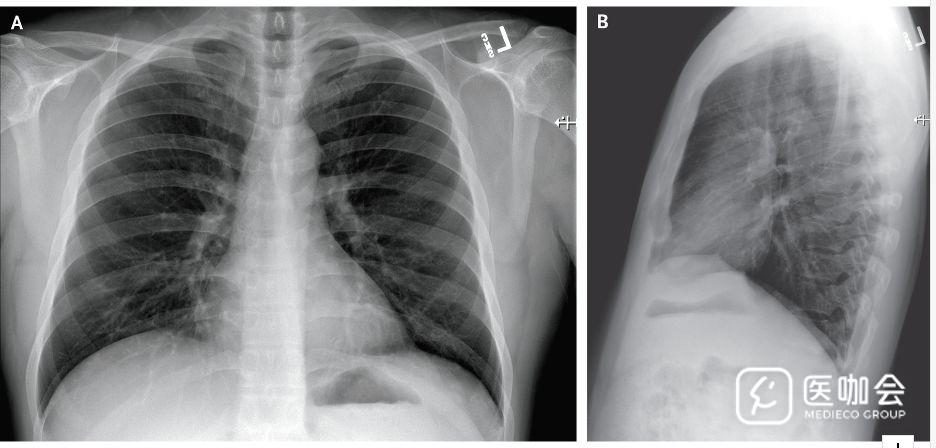

患者住院第3天(患病第7天)时,胸片仍未显示浸润或异常表现(图3)。但是,在住院第5天(患病第9天)晚上的胸片显示,左肺下叶有肺炎表现(图4)。

图3. 患者住院第3天(患病第7天)的胸片

图4. 患者住院第5天(患病第9天)的胸片